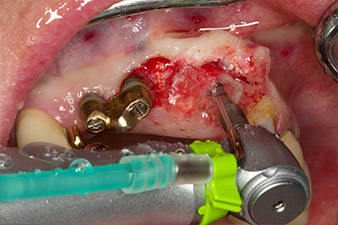

Following primary healing, the soft tissues were shaped using the basally lined bridge. Two months later the site was exposed by a slightly palatal alveolar ridge incision (Fig 2). The dimensions of the alveolar bone proved to be sufficient at position 22. Figures 2 and 4 show the preparation of the implant bed, the tapping and the implantation using Implantmed.

pilot drilling is performed with the new Implantmed and the WS-56 L contra-angle handpiece

Fig. 2: Two months later the pilot drilling is performed with the new Implantmed and the WS-56 L contra-angle handpiece (programme P1, ratio 1:1). The cooling is performed via the spray tube positioned on the left (for right-handed users).